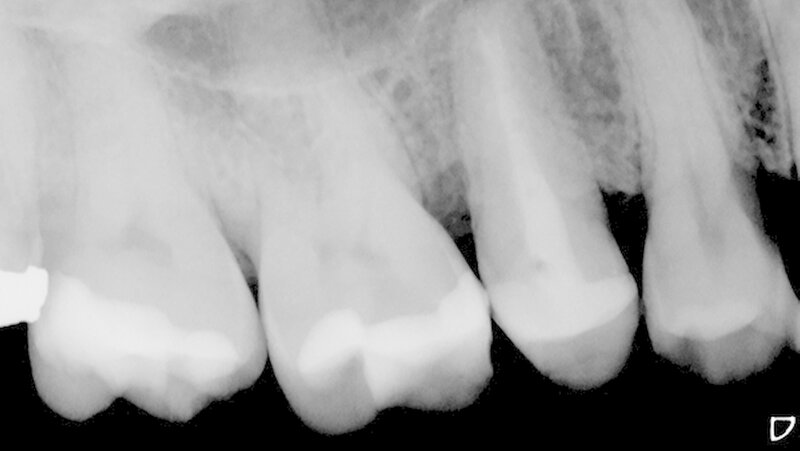

In der Poliklinik für Zahnerhaltung des Universitätsklinikums Münster war zwar die allgemeinmedizinische Anamnese unauffällig, doch zeigte sich klinisch nach Entfernung der vorhandenen mod-Glasionomerzementfüllung ein deutlicher Frakturspalt in mesial-distaler Ausrichtung am Boden der Kavität (Abbildung 1). Darüber hinaus war auf der Röntgenaufnahme des Vorbehandlers eine apikale Aufhellung zu erkennen (Abbildung 2).